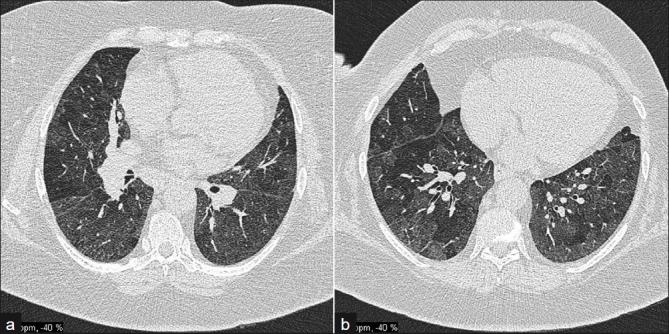

Obliterative bronchiolitis

- rare

- women with well-established RA

-

dry cough and rapidly progressive dyspnea

- poor prognosis

- CXR may be normal

- HRCT shows geometric mosaic attenuation

- expiratory scans confirm air trapping

http://www.ncbi.nlm.nih.gov/pmc/articles/PMC3177462/